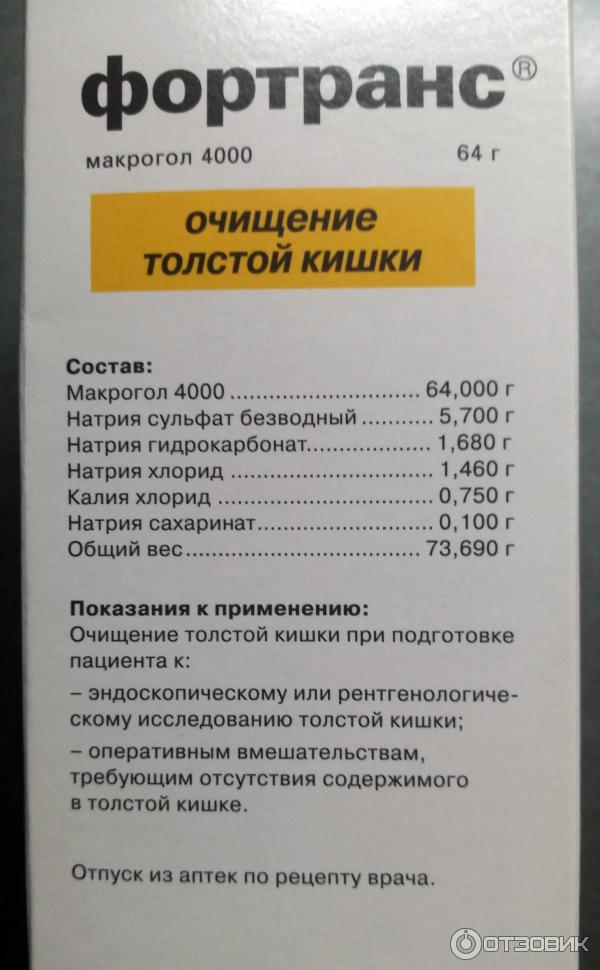

Подготовка к ирригоскопии: необходимые препараты